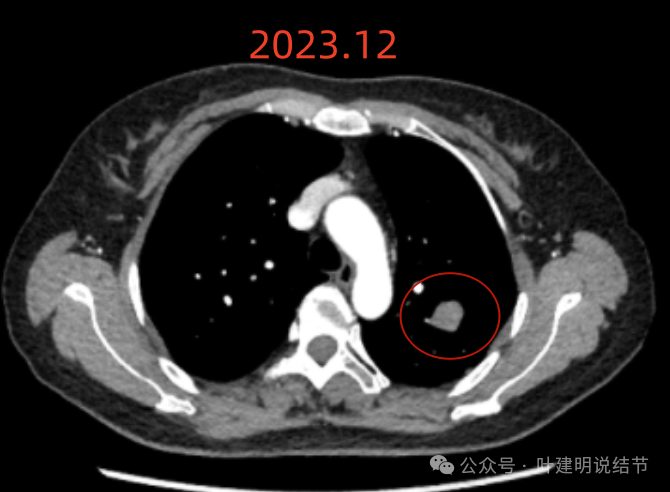

纵隔窗增强见血管与病灶没有间隙,病灶内部密度不均。

左上叶这个病灶看影像感觉边缘比较光滑,内部密度较为均匀,似乎是良性的。但我们如果将其2019年到2023年底的最大层面的影像放在一起对比,病灶是逐渐有增大的。2023年12月的肿块出现浅分叶、整体感觉鼓鼓的,原来病灶与旁边血管是有距离的,但最近这次的已经紧贴着了。但在纵隔窗看,病灶并无钙化或内部坏死密度,说明不太符合肉芽肿性炎或慢性炎性病灶。我觉得要十分倾向恶性肿瘤!低度恶性或交界性肿瘤可能性大。之前我碰到过随访10年的边缘光滑的实性病灶,从3厘米增大到8厘米多,术后是神经内分泌肿瘤的。我的想法还是要考虑切了,术前也可再复查下PET-CT,看看代谢是否活跃。但其实即使代谢轻度增高,也是放着不放心的。若是无代谢的,当然则与恶性不太符合(这种可能性是小的,无代谢不可能又增大)。这个位置穿刺可试试,但有点深,是否可行要与穿刺实施的科室医生沟通看看,若穿刺恶性仍得开刀,穿刺没见到癌细胞,但随访增大仍不放心。个人其实不是特别推荐穿刺。意见供参考!